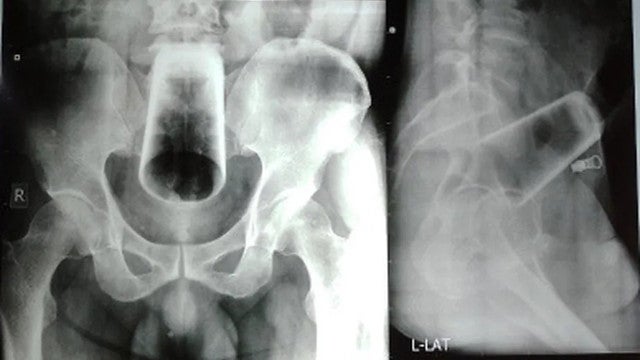

Um paciente no Nepal precisou passar por uma cirurgia para remover um copo de vidro que havia inserido no ânus. Segundo o relato dos médicos, ele esperou três dias antes de procurar ajuda no Nepal Medical College and Teaching Hospital, segundo reportou o Jornal Extra.

Inicialmente, ele tentou remover o objeto sozinho, mas sem sucesso. Os médicos afirmaram que o paciente sentia dor, mas que seu abdômen não estava inchado e ele também não apresentava lesão anal ou sangramento.

Ainda de acordo com o Extra, após várias tentativas para remover o objeto, a equipe decidiu realizar uma enterotomia sigmóide, e o objeto finalmente foi removido. A inserção de objetos retais não é incomum, com casos envolvendo garrafas, recipientes de desodorante e até baterias. A maioria dos casos em homens ocorre naqueles entre 30 e 40 anos e envolve consumo de álcool.